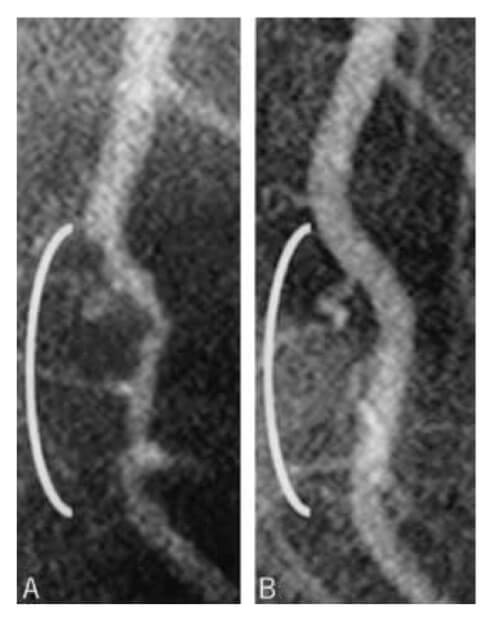

Over a mean duration of 3.7 years, 13 of the 21 non-adherent patients experienced cardiac events, while only one of the 177 diet-adherent patients experienced a cardiac event (stroke). The results “confirm[ed] the capacity of WFPB nutrition to restore health in ‘there is nothing further we can do’ situations,” the study authors wrote. Researchers included a before-and-after arteriogram (right) of one participant’s coronary artery showing clear stenotic reversal.